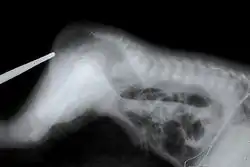

![]() تظهر الأشعة السينية حالة رتق بالشرج التصنيف والمصادر الخارجية تظهر الأشعة السينية حالة رتق بالشرج التصنيف والمصادر الخارجية | |